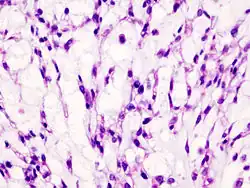

Histopathology